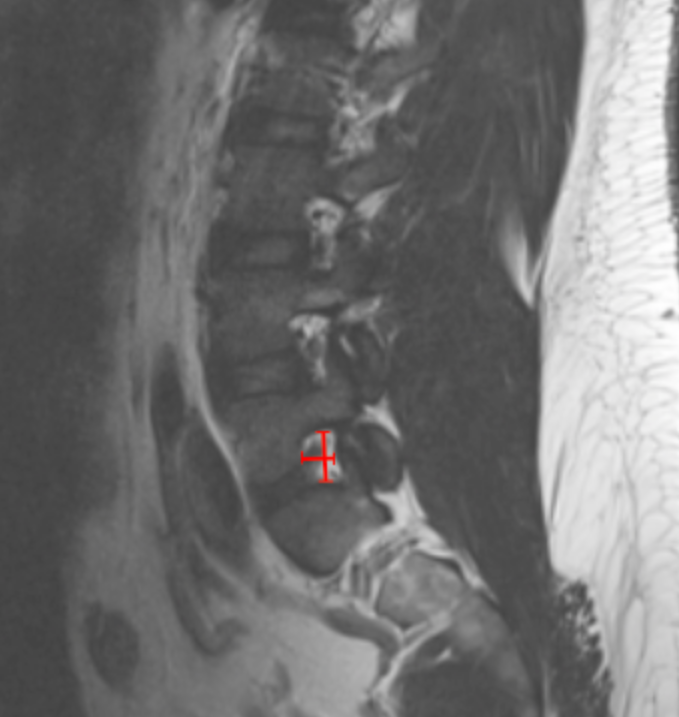

Image Type Lumbar Spine X-Ray CT Scan MRI Scan Anteroposterior (AP) Canal Diameter Cauda Equina Nerve Root Area Conus Medullaris Level Cross-Sectional Area (CSA) of Spinal Canal Disc-Height Index (DHI) Disc Herniation Size Disc Herniation Types Dural Sac CSA Epidural Fat Thickness Filum Terminale Thickness Foraminal Height and Width High-intensity Zone (HIZ) Lateral Recess Width/Depth Modic Endplate Changes (Type I, II, III) Modic (Marrow Signal) Changes Pfirrmann Classification (I-V) Vertebral Bone Quality (VBQ) Score Vertebral Endplate Defects